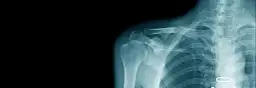

Inwazyjne badania diagnostyczne, takie jak endoskopia, kolonoskopia czy biopsja, a także wszelkiego rodzaju zabiegi chirurgiczne, niosą ze sobą naturalne ryzyko powikłań. Mogą one obejmować krwawienia, infekcje, uszkodzenia narządów czy reakcje na znieczulenie. Ponadto, nadmierne narażenie na promieniowanie rentgenowskie, choć często niezbędne do postawienia trafnej diagnozy, również może mieć długoterminowe negatywne konsekwencje dla zdrowia.